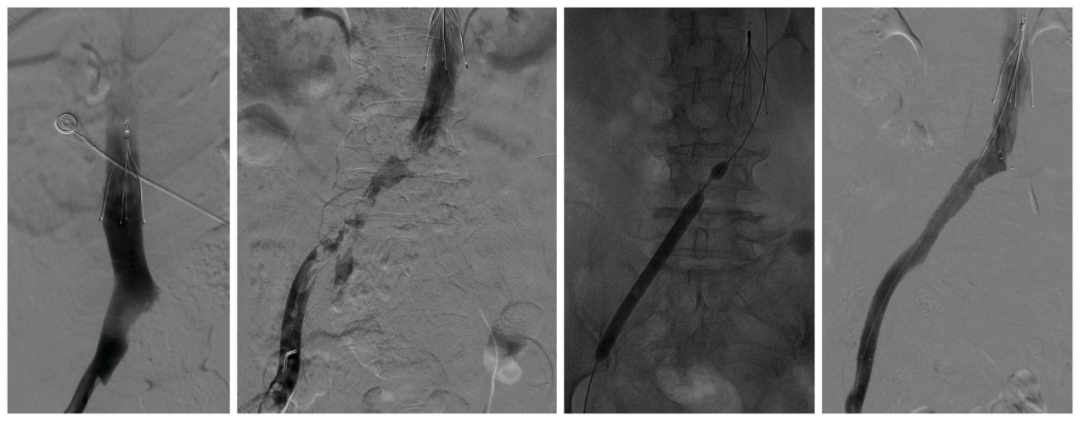

病情紧急,在与患者家属交流同意后,一场深夜急诊手术随即进行。手术由济宁市第一人民医院血管外科孟冉冉主治医师完成,在下腔静脉滤器置入后,进行AngioJet吸栓加球囊扩张加支架植入,经过紧急救治,患者感觉下肢肿胀疼痛缓解,左下肢皮肤颜色及温度逐渐恢复正常,后在管床大夫付顺医师及护理人员的悉心照料下,患者最后痊愈出院。